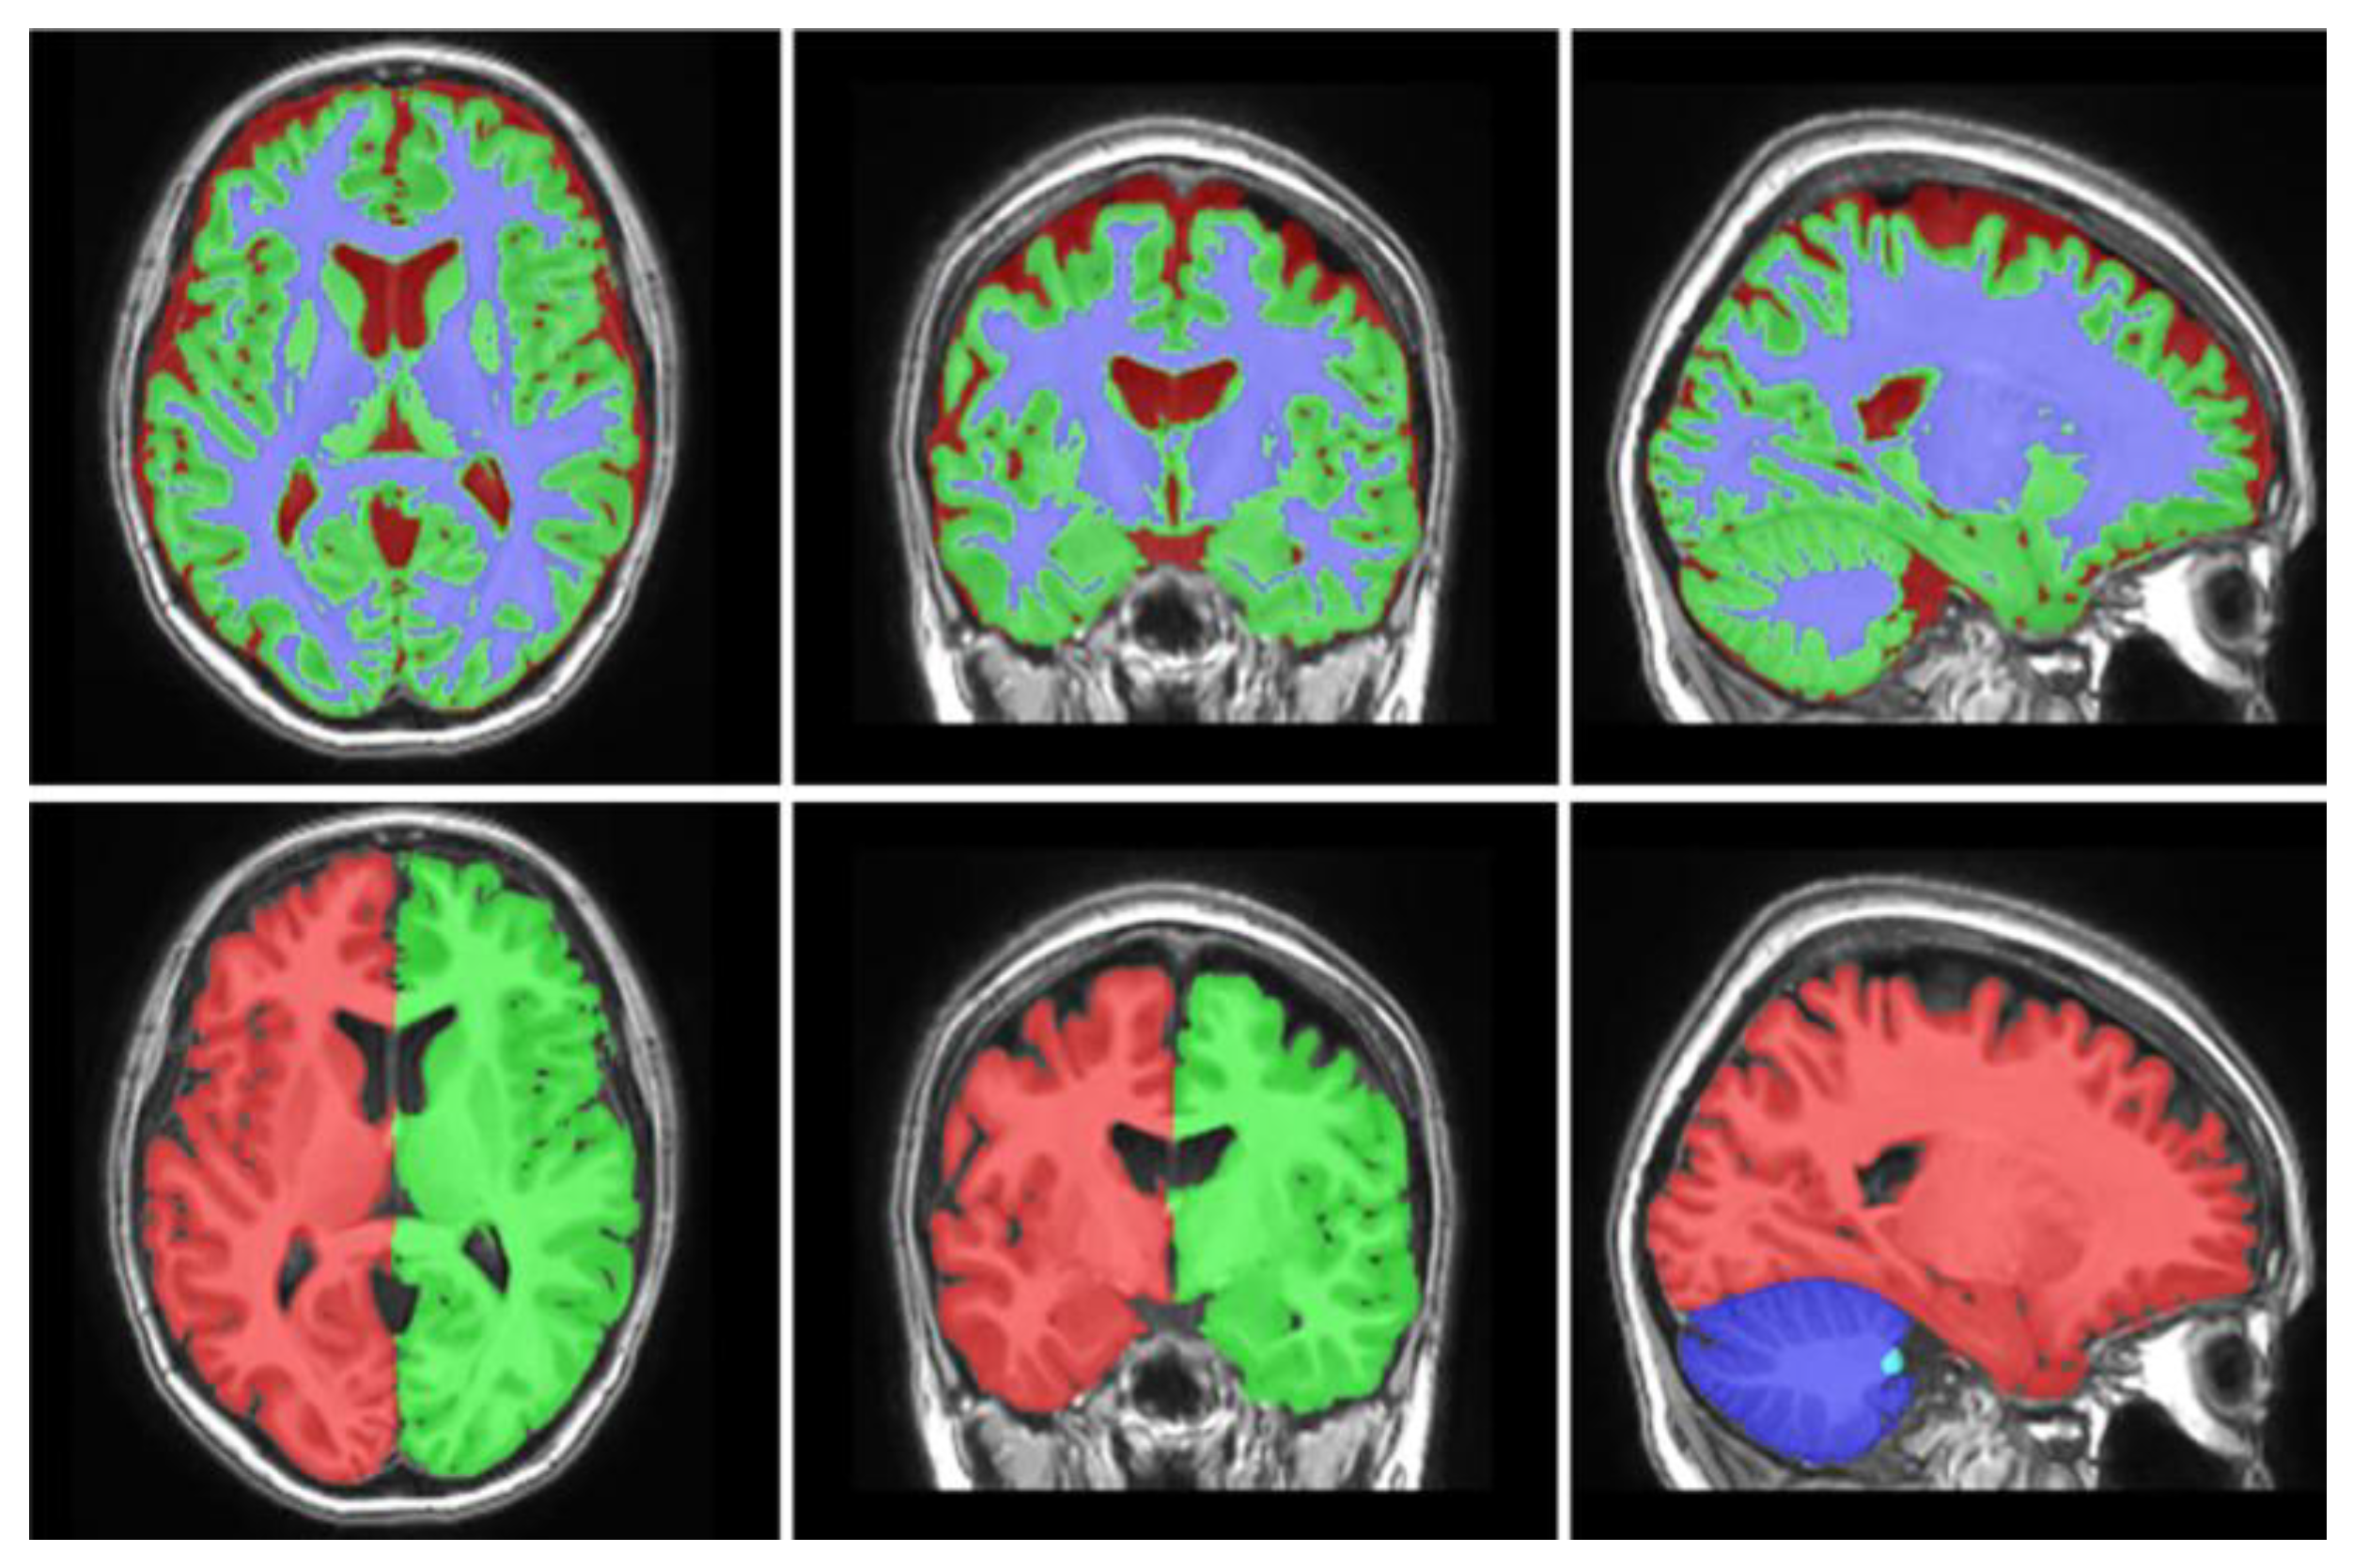

2.2. Imaging and Morphometrical Data Collection